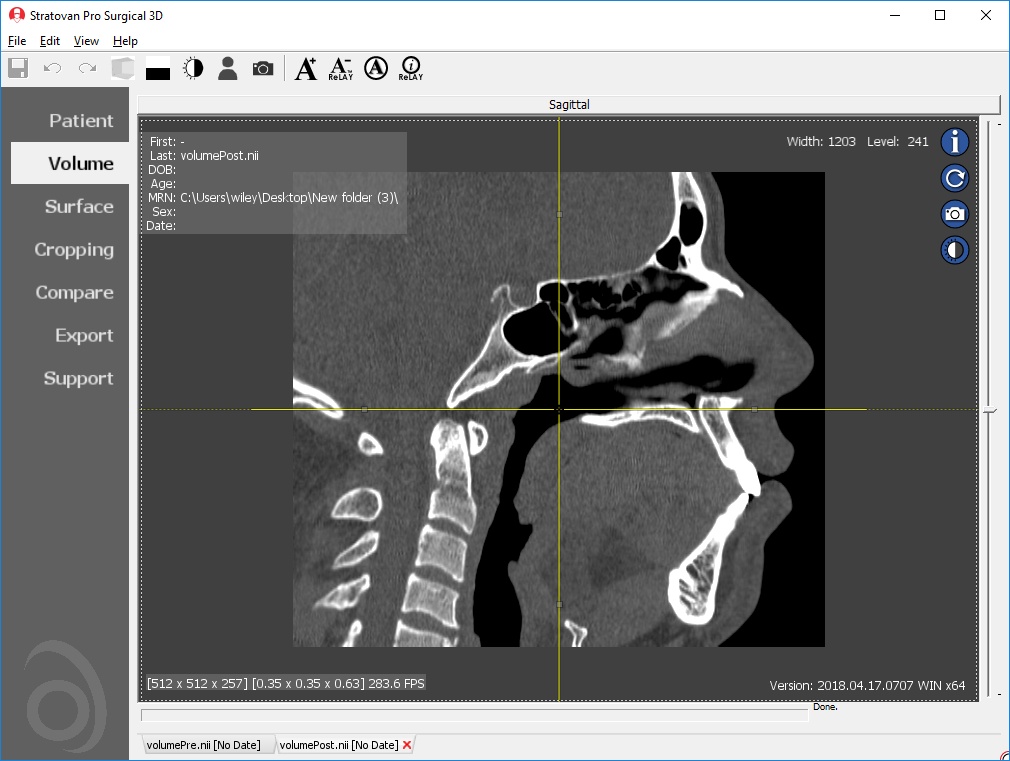

Multi-planar slicing.

Oblique slicing.